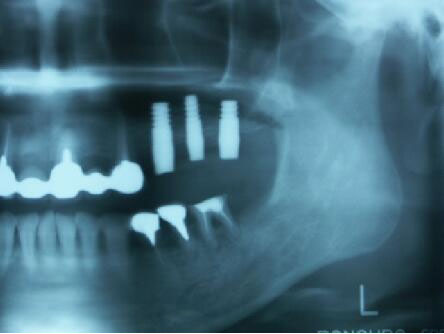

インプラント埋入2ヵ月後のエックス線写真と口腔内写真

インプラント体(フィクスチャー)の周りに骨が出来始めている

4ヵ月後のエックス線写真

4ヵ月後に最終かぶせ物をしてメンテナンスへ